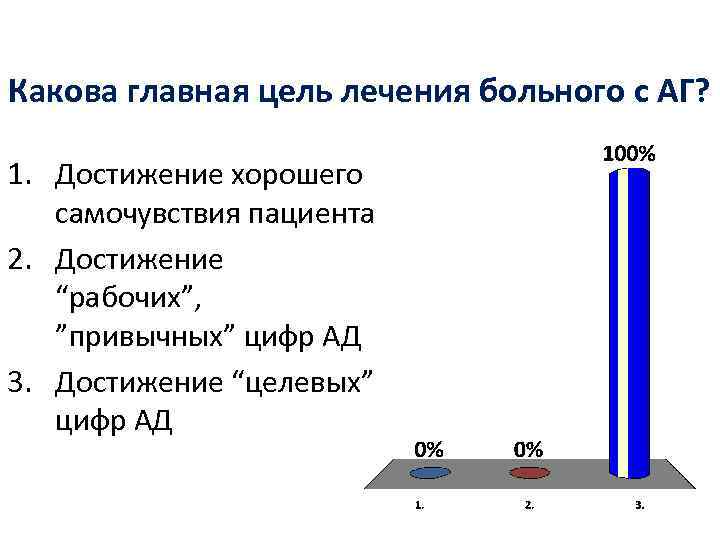

Какова главная цель лечения больного с АГ? 1. Достижение хорошего самочувствия пациента 2. Достижение “рабочих”, ”привычных” цифр АД 3. Достижение “целевых” цифр АД

Какова главная цель лечения больного с АГ? 1. Достижение хорошего самочувствия пациента 2. Достижение “рабочих”, ”привычных” цифр АД 3. Достижение “целевых” цифр АД